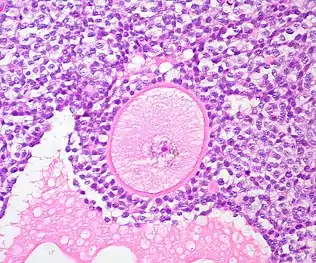

A common source of ovarian tissue used comes from tissue excised from the patient prior to cancer treatment, which is then cryopreserved.[7] The tissue is then cultured to activate the primordial follicles and allow them to develop.[2] To isolate the follicles, a combination of enzymatic and mechanical tissue digestion has shown to be the most effective method to yield a high quantity of follicles whilst maintaining their quality.[8] The enzymes used, liberase DH and DNase, are produced by good manufacturing practice (GMP) to fully comply with GMP guidelines to ensure future application to patients. The enzymatic digestion process is inactivated every 30 minutes and the suspension is filtered to allow fully isolated follicles to be removed and reduce unnecessary enzyme exposure which may lead to damage of their basement membrane and their death.[8]

The isolated follicles are then encapsulated within a 3D matrix and cultured for up to 4 weeks.[7] The material used has to meet biosafety and clinically compatible standards, such as adequate protection and support of the follicles and adaptability to human body temperature, if artificial ovaries are to be transplanted into a patient.[5] Potential materials are divided into synthetic polymers and natural polymers.[8] Synthetic polymers tend to be more predictable than natural polymers in terms of their rate of degradation and their mechanical properties can be tailored to the specific clinical requirements.[8] Although they contain no essential molecules for cell adhesion, bioactive factors can be incorporated to stimulate this.[8] The only synthetic polymer utilised so far has been poly(ethylene glycol), which developed immature mouse follicles into antral follicles and corpora lutea.[8][5]

The microenvironment of the structure should mimic that of the natural ovary, so the artificial ovary should support the follicles structurally, but also cellularly.[8] Ovarian stromal cells are integrated into the microenvironment as they play an important role in early development of the follicles.[8] They release various factors which positively regulate the transition of primordial follicles to primary follicles, but also release other cells which will differentiate into theca cells; those that play a supportive role for growing follicles and produce sex steroids such as androstenedione and testosterone.[8] This can be achieved by isolating them from a second fresh ovarian biopsy once the patient has completed their cancer treatment, thus avoiding potential contamination.[8] Endothelial cells should also be co-transported as they are key to promoting angiogenesis of the artificial ovary.[8]

The majority of knowledge we have about the artificial ovary has been discovered through the use of mouse models. Initial experiments in the 1990s were performed on mice that saw the grafting of preantral follicles onto an artificial ovary made with collagen.[8] The preantral follicles were shown to undergo in vitro growth (IVG) therefore suggesting that a collagen matrix could be of good use for an artificial ovary.[8] Despite the positive results, the growth was accompanied by atresia of antral follicles meaning that it was necessary to look for other alternatives to collagen that allowed follicle growth when the artificial ovary was implanted back into the mouse.[8]